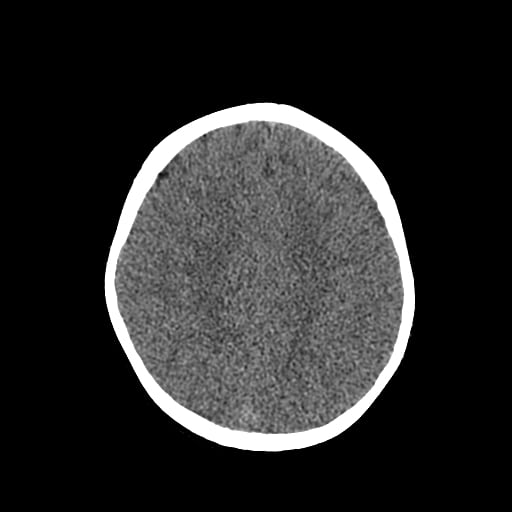

Age: 1

Sex: Male

Indication: Fall